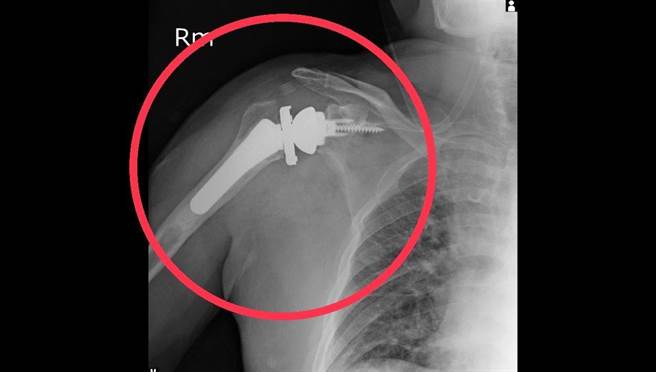

林口长庚运动医学骨科医师邱致皓说明,新一代的反转式全人工肩关节置换设计利用三角肌取代旋转肌,得到更好的效果。(大里仁爱医院提供/潘虹恩台中传真)

林口长庚运动医学骨科医师邱致皓说明,传统全人工肩关节置换手术,病人需保有完整的旋转肌肌腱才能有完整的功能,新一代的反转式全人工肩关节置换设计利用三角肌取代旋转肌,得到更好的效果;目前健保也将大范围旋转肌肌腱破裂或肩盂骨性缺损,合併肩关节重度病变或无法修补,重大失能且65岁以上的患者纳入全额给付,若通过健保审查可帮病人省下高额的自费支出。